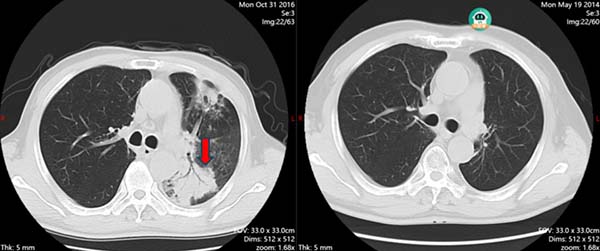

然而,与癌症的博弈,永远充满了意想不到的转折。八年前,他再次出现咳嗽气短。当在他的左肺发现新的阴影时,我们所有人的心都揪紧了——最担心的“复发”难道来了吗?

但医学需要的是证据。我们一遍遍地为他进行气管镜、痰检、甚至穿刺活检。这个过程对患者而言,是巨大的身心煎熬。就在我们高度怀疑肿瘤时,病原学证据却指向了一个令人意外的方向:堪萨斯分枝杆菌感染——这是一种非结核分枝杆菌。我们立刻调整航向,转向抗感染治疗。

虽然过程曲折,但排除了肿瘤复发,这本身就是一个好消息。经过一年的抗感染治疗,他的病灶稳定了。这次经历,像一场突如其来的大雾,我们一度迷失,但最终凭借细致的侦查,找到了正确的出路,也再次守护了他的健康。